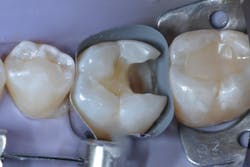

Caries lesions were removed and air abrasion was employed to remove impurities on the unprepared tooth surfaces and create increased surface area for bonding. Preparation of the class II carious lesions revealed demineralization on the adjacent tooth structure (figure 3). When lesions such as these are discovered, dentists are often at a crossroads whether to intervene or monitor the area for progression. It is my experience that these early caries lesions can be predictably arrested with resin infiltration (figure 4), and that no intervention usually results in the progression of caries.

In this case, lateral access was achieved by the preparation of the adjacent teeth as part of the proposed treatment plan. Early caries lesions that are noted on radiographs that are not accessible in cases such as this one can be accessed by placing an orthodontic spacer. This patient was restored with direct composite bonding (figure 5) and these restorations have proven to have a favorable long-term outcome (figure 6).